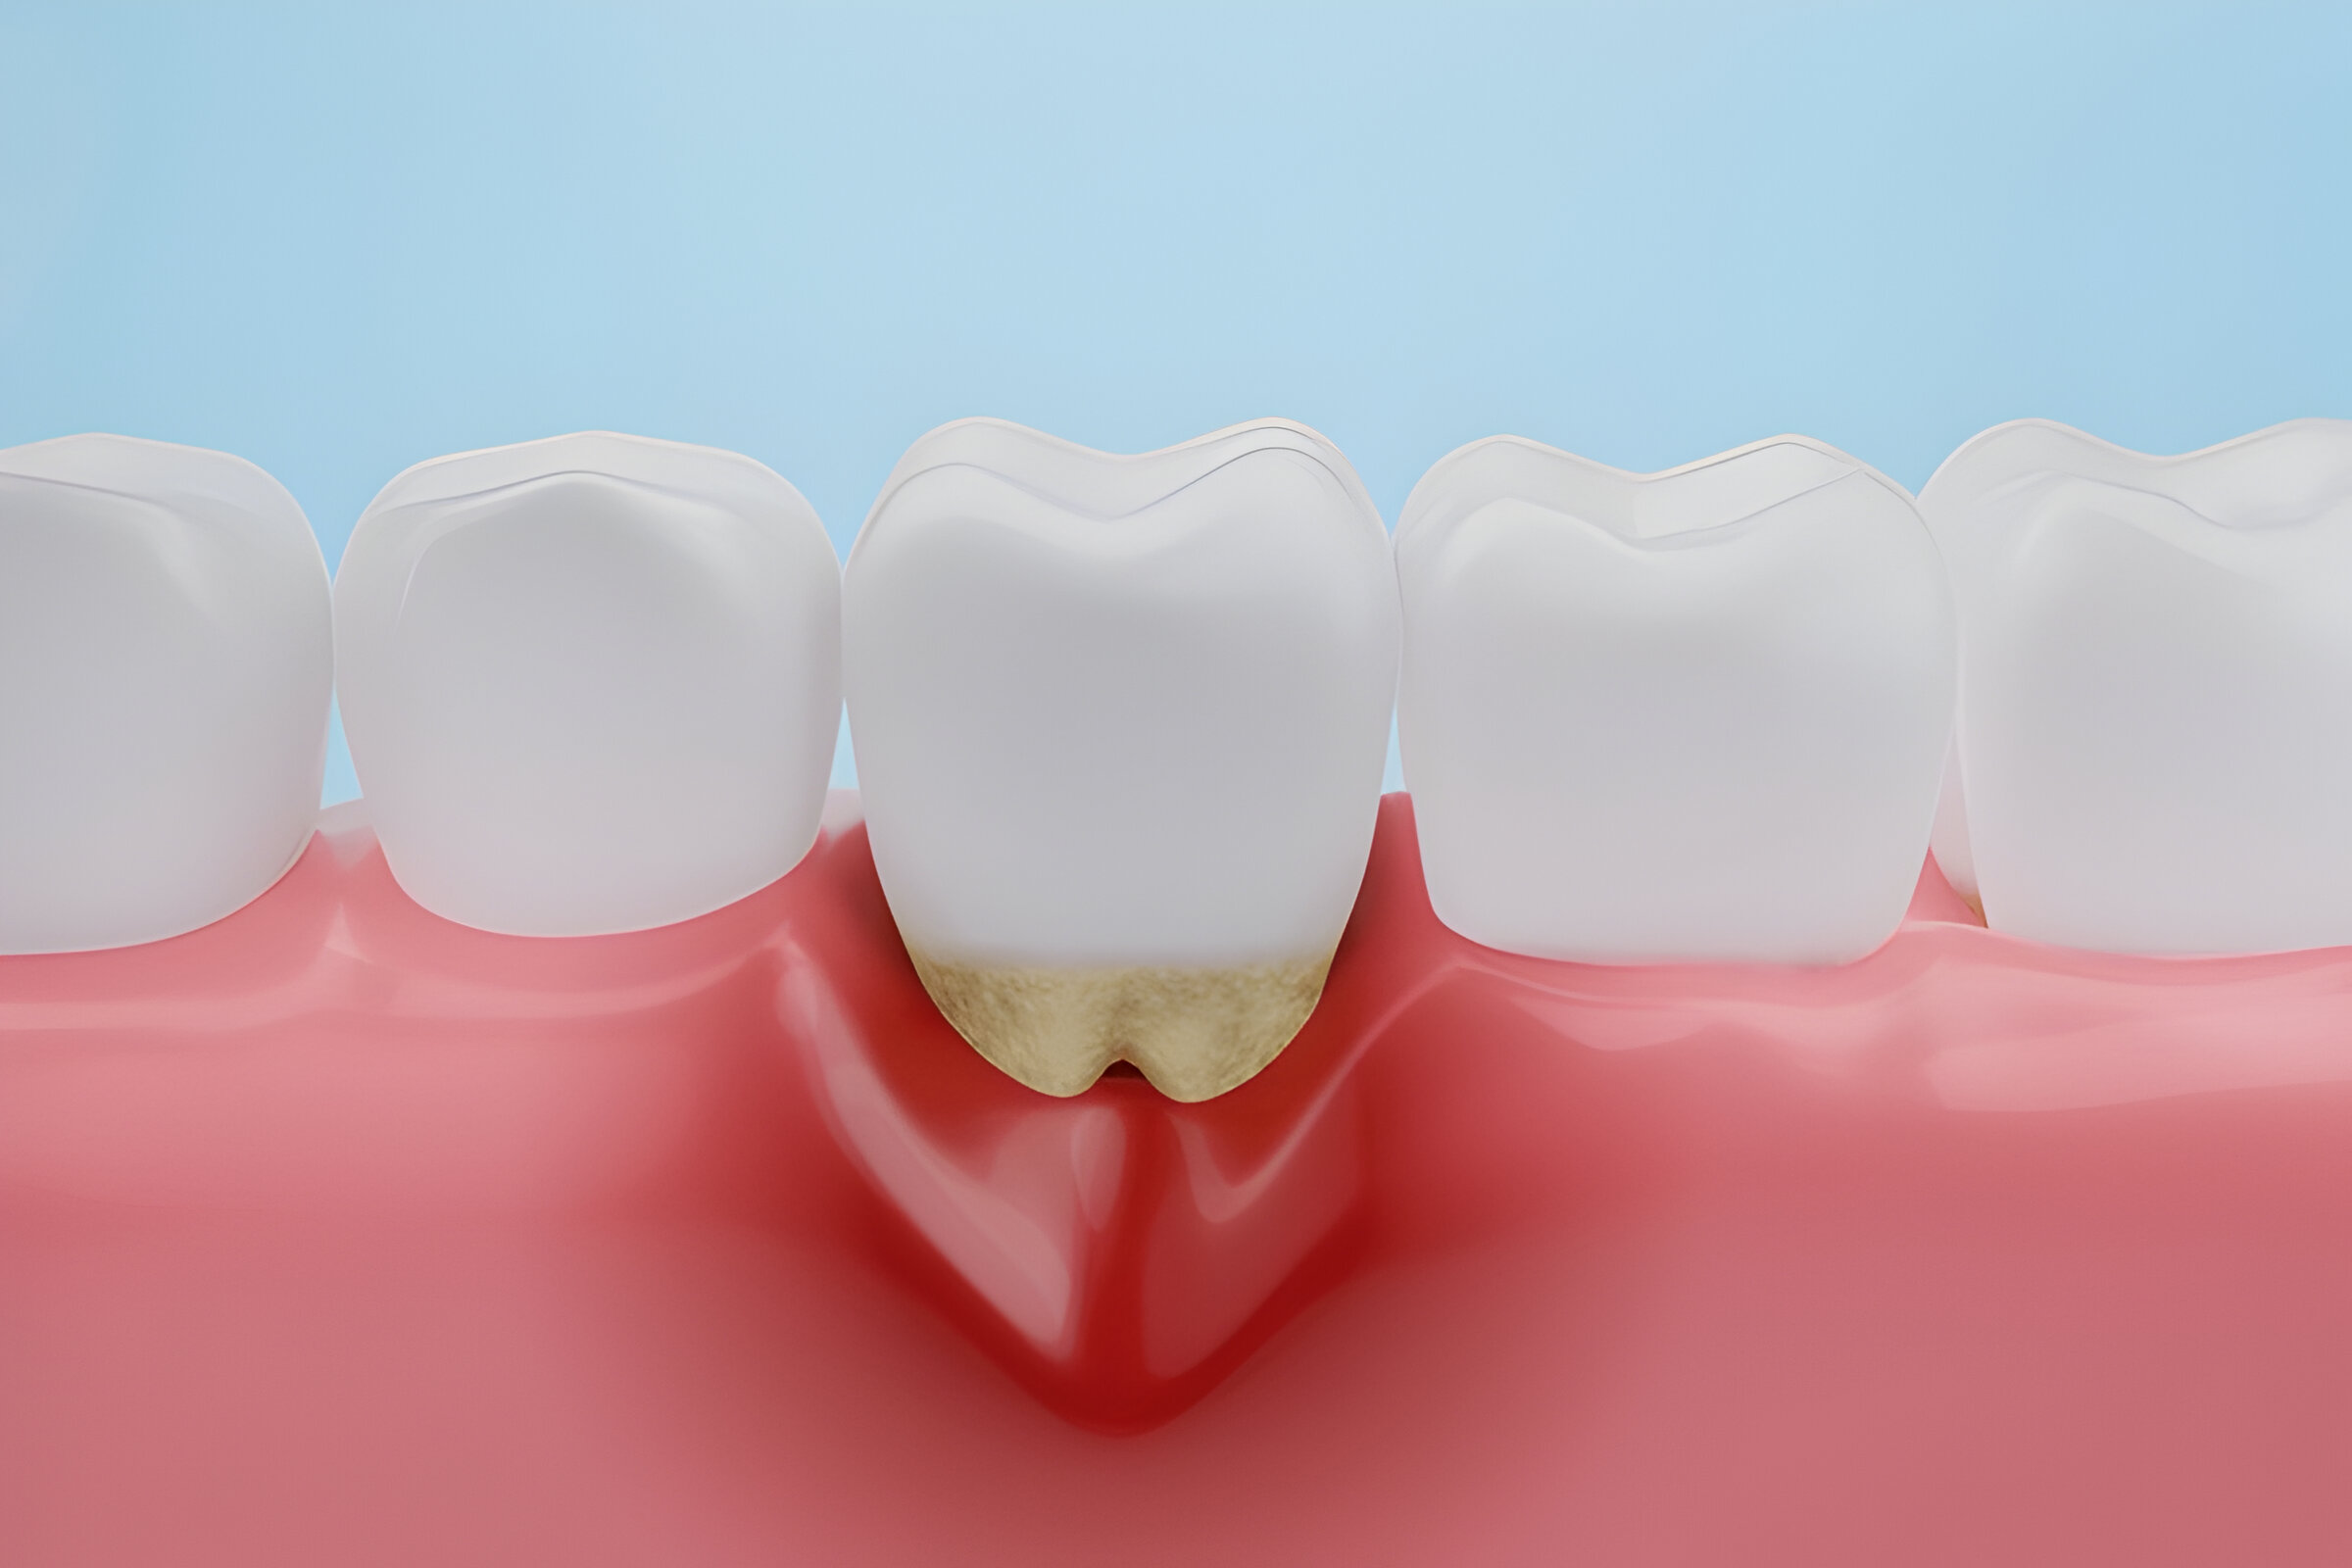

Protect your smile in Balwyn North from gum disease with our expert dental care. Visit us for comprehensive treatments and prevention strategies to maintain optimal oral health. Gum Disease Treatment in Balwyn North